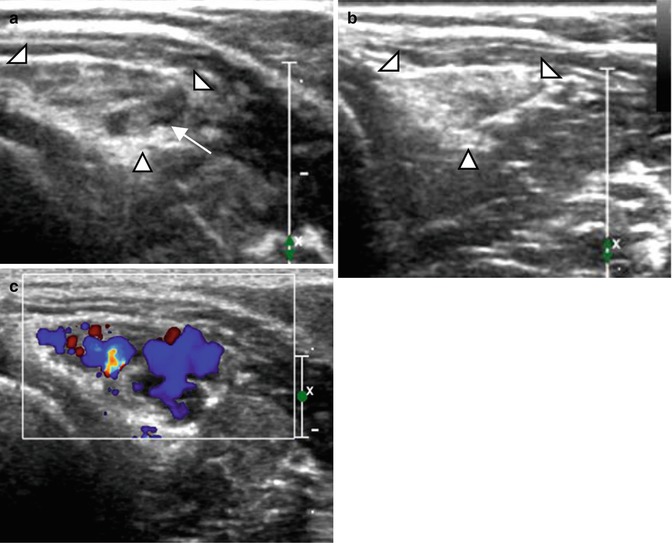

Five-year-old girl with intramuscular venous malformation. (a) Ultrasound image. (b) Ultrasound image after local compression. (c) Color Doppler image. (a) Ultrasound image shows a heterogeneous lesion (arrowhead) with internal fluid component (arrow). (b) The lesion is compressible (arrowhead). (c) After decompression, filling of the cavities (vessels) can be observed on color Doppler US